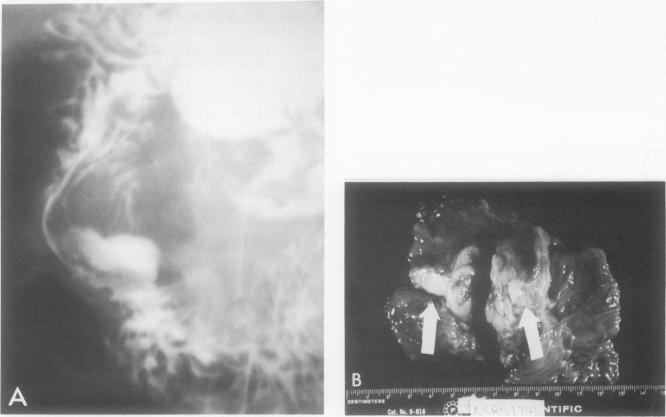

保留幽门的胰十二指肠切除术。临床与生理学评估。

Pylorus-preserving pancreatoduodenectomy. A clinical and physiologic appraisal.

Since 1978, 252 patients from different centers in the world have undergone pylorus-preserving pancreatoduodenectomy. Fifty-five per cent of the patients had malignant tumors in the region of the head of the pancreas. The overall operative mortality rate was 2.8%. Anastomotic leakage and fistulae occurred in 19% of the patients. Pancreatic, biliary, and enteric fistulae represented 11%, 4%, and 4%, respectively. Peptic ulcers were subsequently diagnosed in seven patients (3%), two of whom required vagotomy and antrectomy. Delayed recovery of gastric function was the most common complication of this operation, with an overall incidence of 30%. Although the cause of this gastric dysfunction is unknown, its transient nature in most patients makes expectant therapy with gastric tube drainage the best remedy when the problem is encountered. Pylorus-preserving pancreatoduodenectomy decreased the incidence of postgastric surgery syndromes that are commonly associated with the standard Whipple operation. The existing data support the continued use of the operation and the need for future laboratory and clinical investigation of its physiologic impact.

自1978年以来,来自世界各地不同中心的252例患者接受了保留幽门的胰十二指肠切除术。55%的患者在胰头区域患有恶性肿瘤。总体手术死亡率为2.8%。19%的患者发生吻合口漏和瘘。胰瘘、胆瘘和肠瘘分别占11%、4%和4%。随后有7例患者(3%)被诊断为消化性溃疡,其中2例需要行迷走神经切断术和胃窦切除术。胃功能延迟恢复是该手术最常见的并发症,总体发生率为30%。虽然这种胃功能障碍的原因尚不清楚,但在大多数患者中它具有短暂性,因此当遇到这个问题时,采用胃管引流的期待疗法是最佳治疗方法。保留幽门的胰十二指肠切除术降低了通常与标准惠普尔手术相关的胃手术后综合征的发生率。现有数据支持继续使用该手术,并支持未来对其生理影响进行实验室和临床研究的必要性。